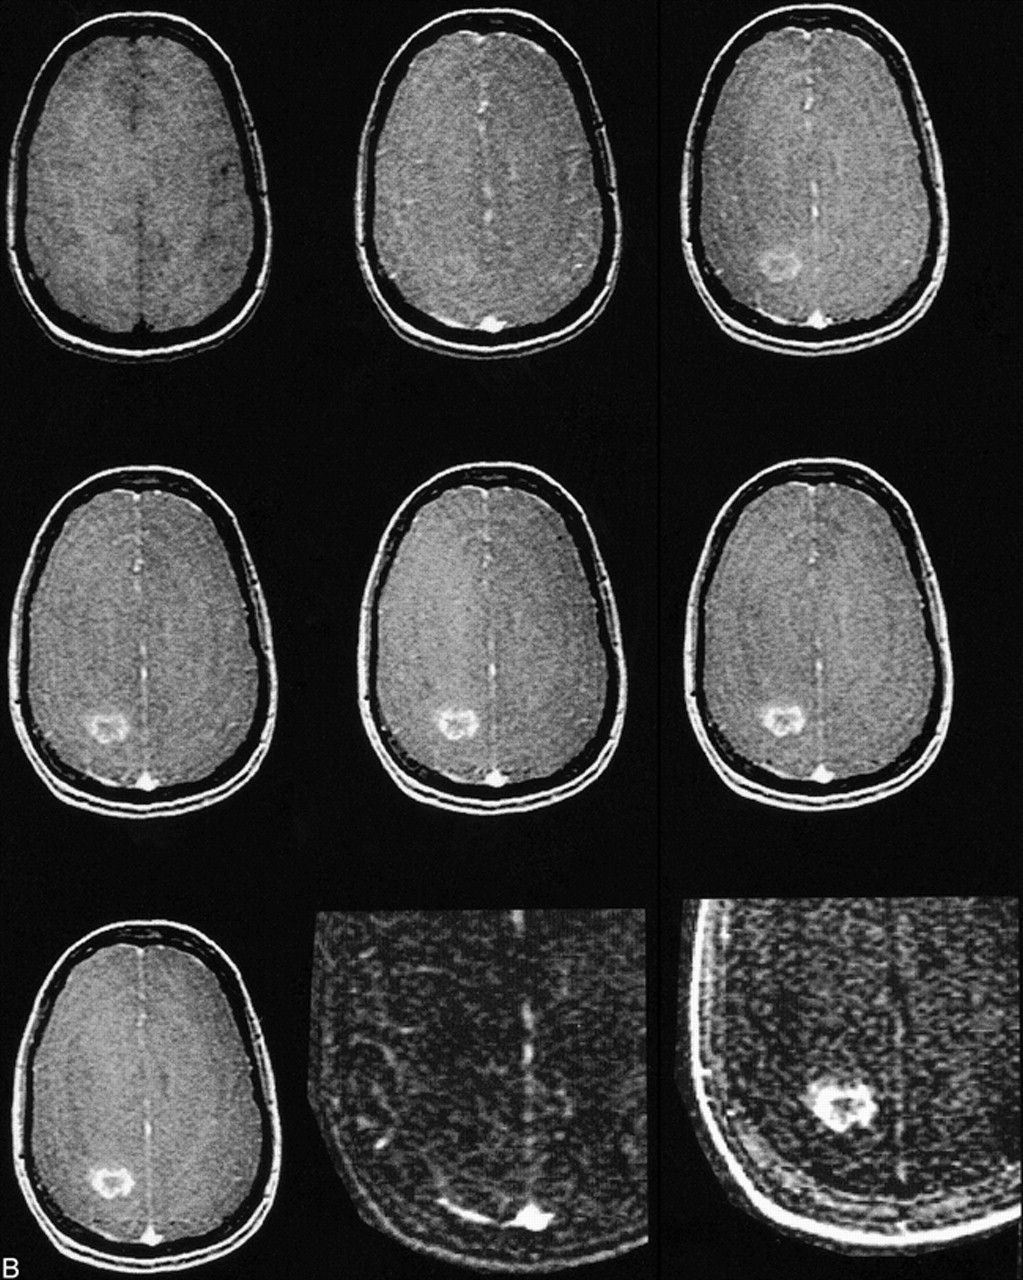

B, MR image before contrast administration (top left) and six dynamic contrast-enhanced MR images of a grade 4 glioblastoma multiforme. Top center, 15 seconds; top right, 45 seconds; middle left, 75 seconds; middle center, 105 seconds; middle right, 135 seconds; and lower left, 165 seconds after contrast administration. From these seven images, spatial maps of fBV and kPS were determined: fBV (lower center) was estimated as 3.0% in the tumor rim and as 0.01% in the core. kPS values (lower right) were 13.6 mL/100 cm3 per minute in the tumor (compared with 0.5 mL/100 cm3 per minute in the core). Times are defined as the time after contrast that the center of k-space (mid-part of 3D acquisition) was attained.

A–D, Fitted curves of the ΔSI time course of a typical low-grade (A, B) and a typical high-grade (C, D) tumor. Dynamic postcontrast values for the reference vascular signal (sagittal sinus) are displayed in A and C, respectively, and for tumor curves in B and D, respectively. The equations are displayed on the graphs. The low-grade tumor (patient 8 in Table 1) has an fBV of 3.2%, k1 + k2 is 5.8, and kPS is 5.5; the high-grade tumor (patient 20 in Table 1) has an fBV of 6.7%, k1 + k2 is 13.7, and kPS is 10.8. Times are defined as the time after contrast administration that the center of k-space (mid-part of 3D acquisition) was attained.